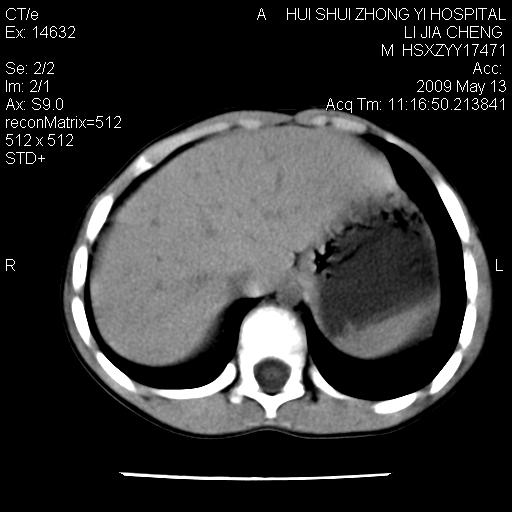

标题: PED1887:男性,6岁。反复脐周疼痛2年余。请各位老师看下腹 [打印本页]

标题: PED1887:男性,6岁。反复脐周疼痛2年余。请各位老师看下腹

该患者可自行好转,大小便未见异常,化验:便未见虫卵,血常规:wbc:8000;淋巴3600,中性45%

脂肪肉瘤可能性大,大血管边界不清,特别是腔静脉。不除外其他腹膜后肿瘤。

是不是有蛔虫哦,楼主图示块影前方肠管壁显著增厚,不除外慢性肠炎或肠壁占位,建议肠道准备后复查

来源于十二指肠水平部病变?建议行进一步检查。